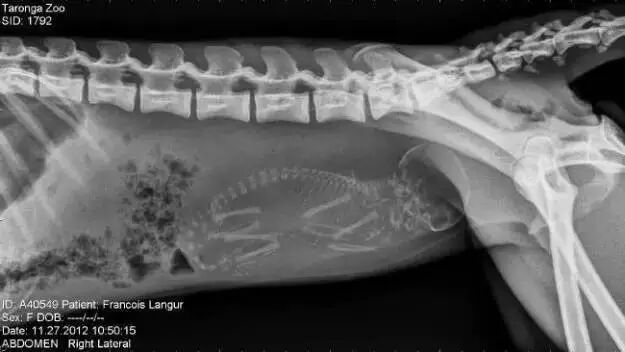

怀孕的猴子

奇趣百科 涨姿势 · 17种怀孕动物X光照片,大开眼界!-怀孕期